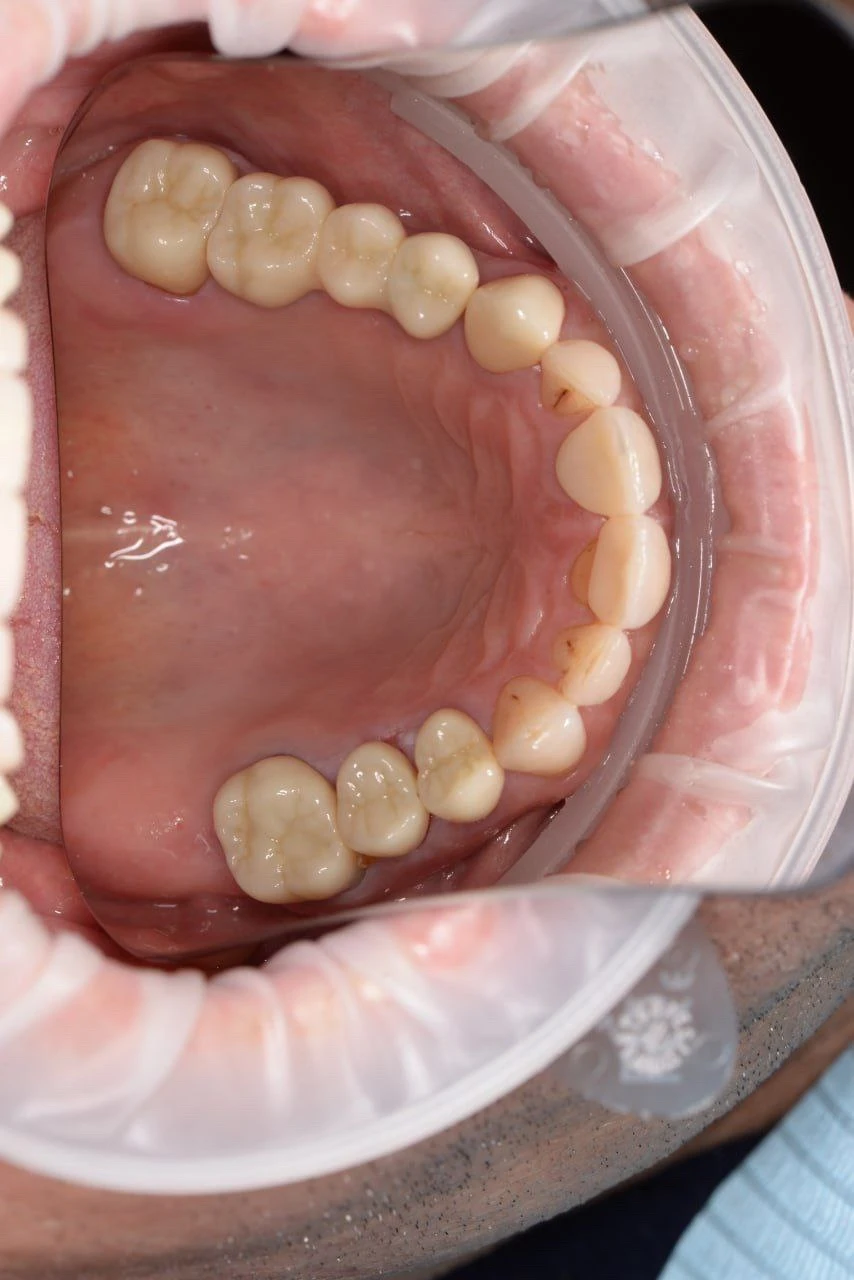

Цирконієва коронка на імпланті 46